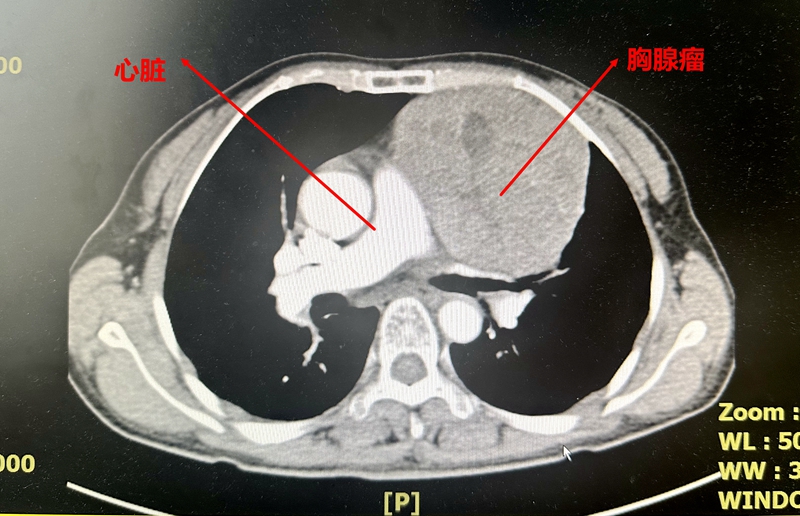

通过影像CT检查,医生发现这个肿瘤位于胸部的前纵膈区,紧邻胸骨后方与心脏上方,其大小几乎与心脏相当。

心胸外科主任林苗经过综合分析,判断这极可能是一个胸腺瘤,需要尽早手术来切除。鉴于肿瘤的体积较大,采用微创手术的风险相对较高,因此,开胸手术成为了最合适的选择。